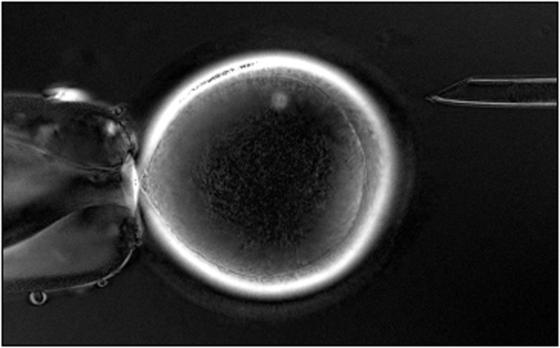

Eine Pipette hält eine Eizelle, der – ebenfalls mit einer Pipette – der Zellkern entfernt wird.

Foto: Shoukhrat M. Mitalipov/Nature/dpa